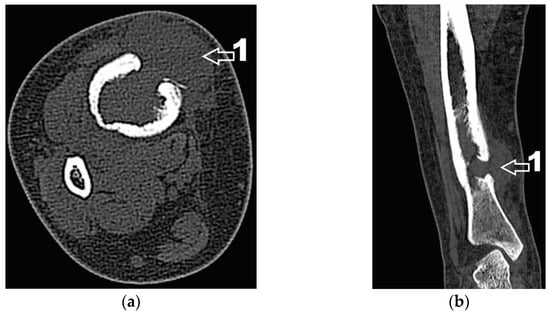

Corroborating the clinical examination with the patient’s history, we had decided to investigate again radiological and imaging (CT, MRI). Radiological and CT examination showed a slight increase in the size of the tumor formation, confirmed by MRI images (Figure 3), at this time the dimensions being 5.5/1.95/2.2 cm. Radiological and CT features were similar, osteolytic lesion with thinning and disruption of the bone cortex, associating periosteal reaction (Figure 4). However, this time, the CT images show the extraosseous expansion of the tumor formation, through the bone window created by the initial biopsy (Figure 5).

Figure 4. (a) CT axial section. 1—disruption of the bone cortex; (b) CT axial section. 1—thinning of bone cortex, 2—periosteal reaction.